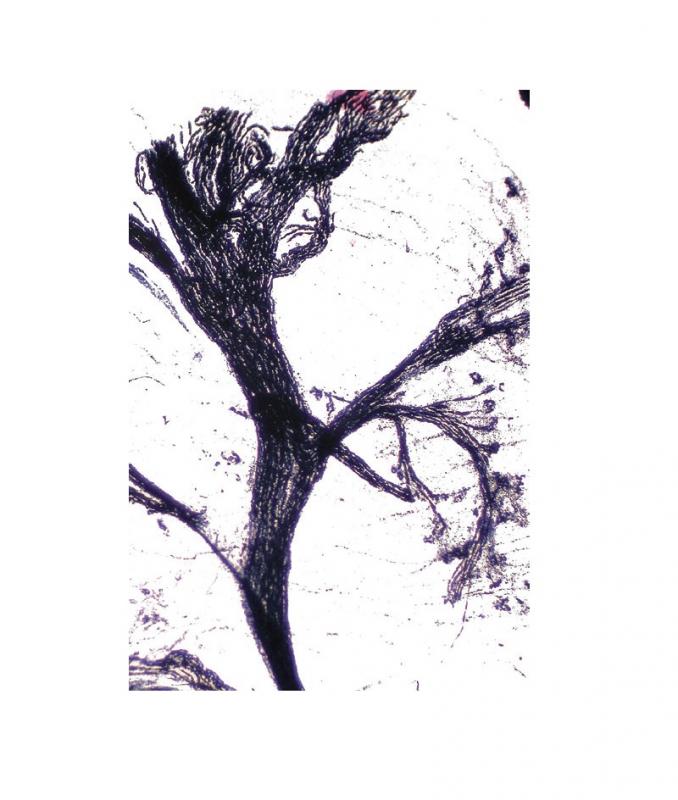

Préparation microscopique: Cellule nerveuse moëlle CT

Référence Interne : S60426